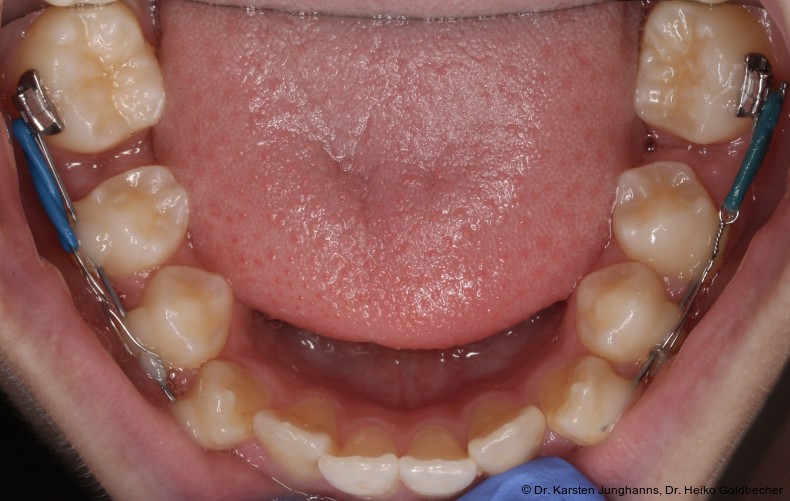

Eine Patientin stellte sich im Alter von neun Jahren erstmals vor. An den ersten Molaren des Unterkiefers wurden vom Hauzahnarzt eine MIH diagnostiziert (Abb. 1a) und die Zähne als nicht erhaltungsfähig eingestuft. Die beiden ersten Molaren wurden hemiseziert und der distale Anteil extrahiert. Gut zu erkennen ist auf dem OPG die annähernd achsengerechte Mesialisierung der zweiten Molaren sowie die Aufwanderung der Zahnkeime der dritten Molaren (Abb 1b: ca. 1,5 Jahre nach Hemisektion). Noch vor Durchbruch der zweiten Molaren in die Mundhöhle wurde auch der mesiale Anteil entfernt. Der spontane Lückenschluss erfolgte innerhalb der nächsten anderthalb Jahre (Abb. 1c). Die endgültige Achsstellung kann nach Ausdehnung der Teilmultibandapparatur eingestellt werden.